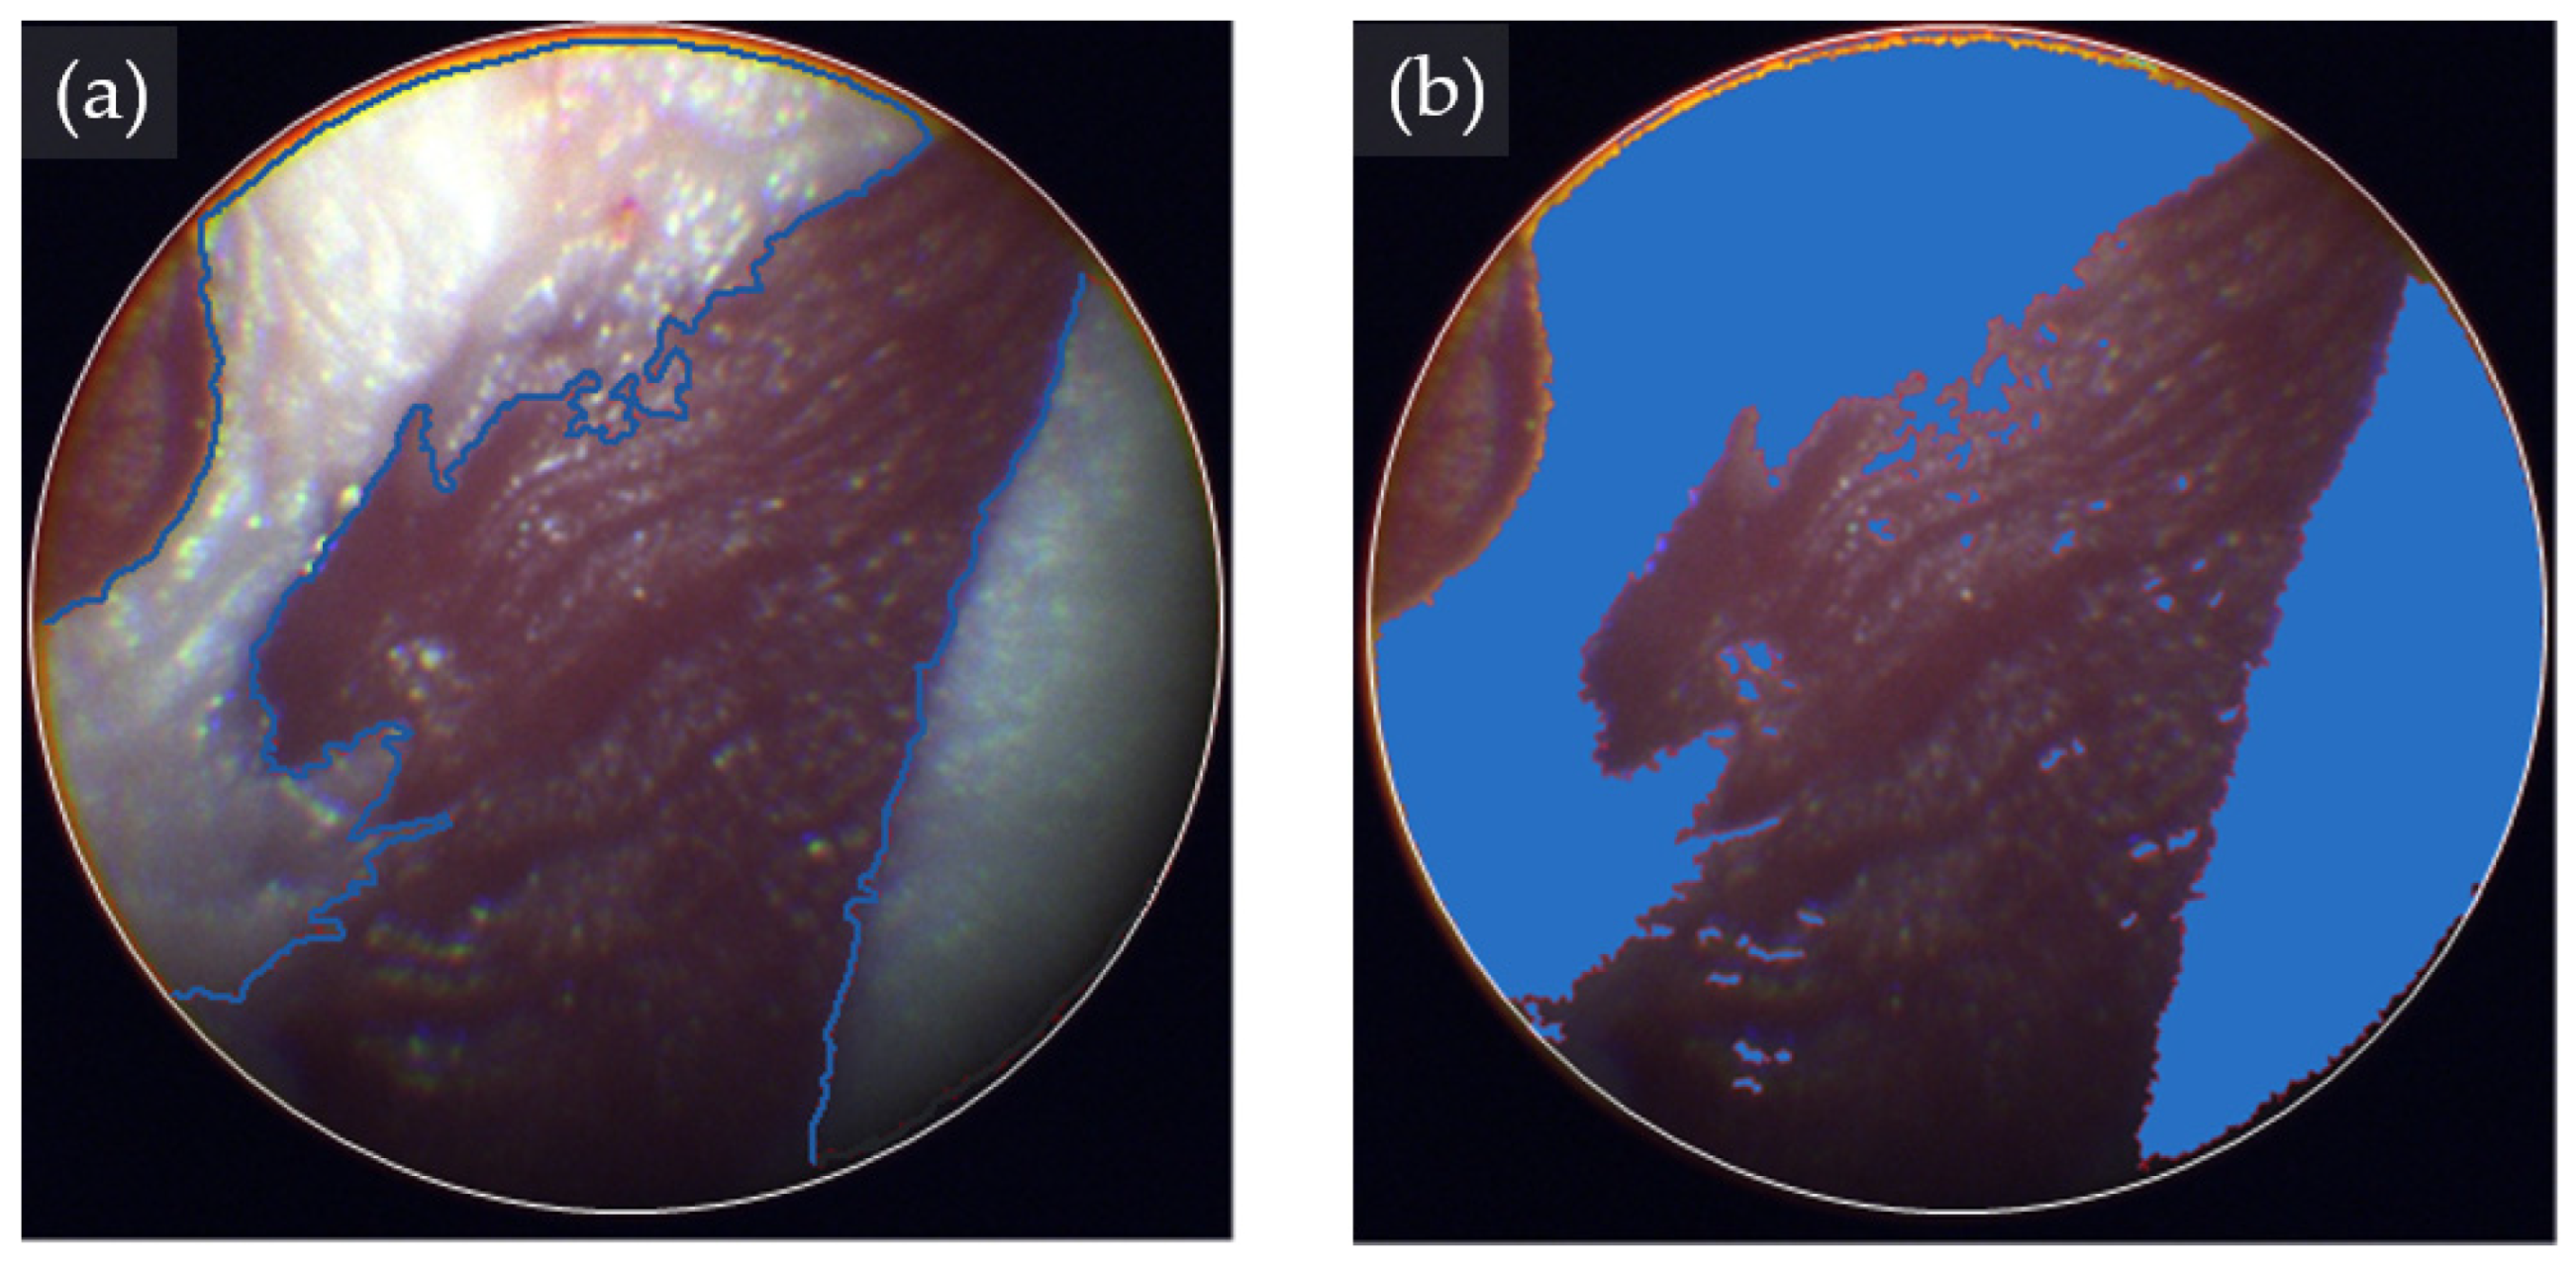

3.2. Tissue Classification Performance of eHSI in Orthotopic Pancreatic Tumors